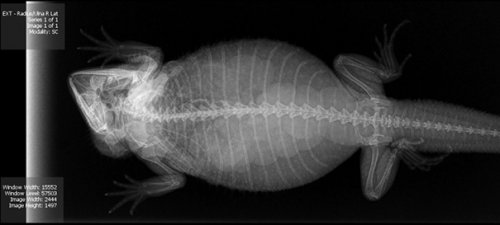

Итак, как выглядят рентгеновские снимки беременных животных:

агама